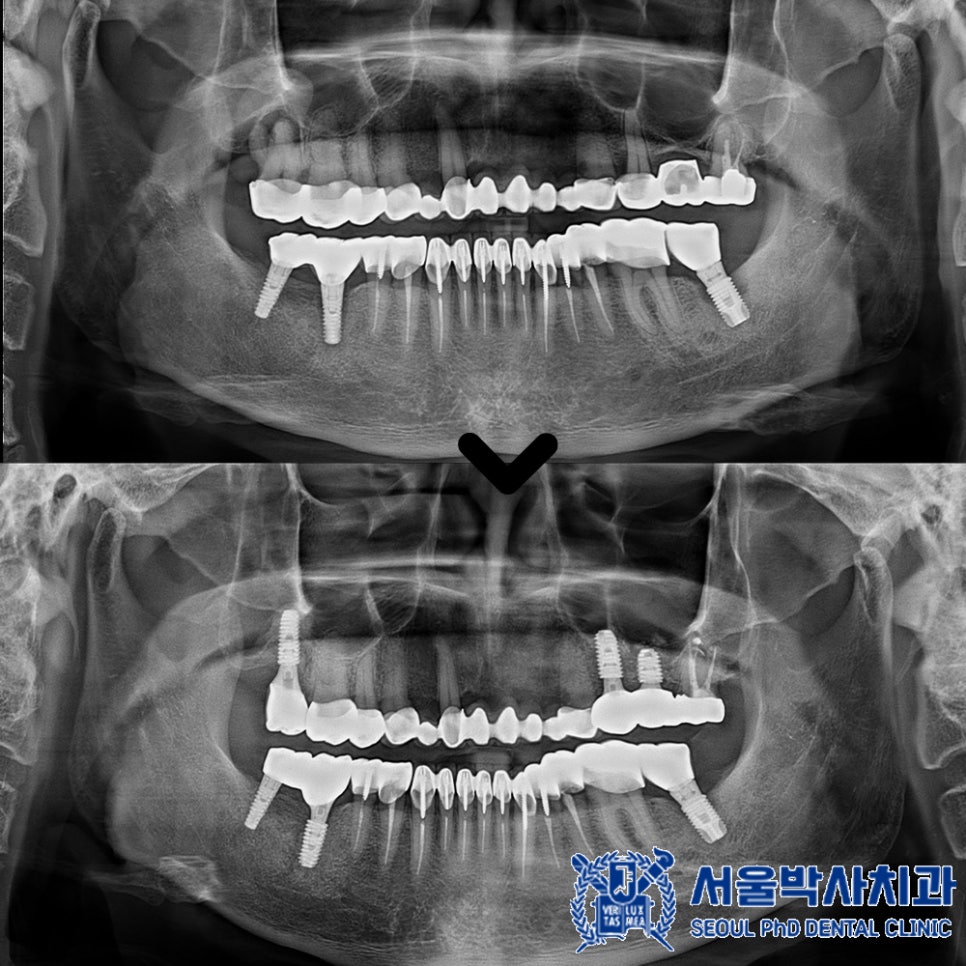

오른쪽 아래 기존 임플란트 중 뒤쪽 큰 어금니는

임플란트와 인공 치아를 연결해주는 부분이 파절되었고

앞쪽 큰 어금니 임플란트는 염증으로 인해

상태가 좋지 않았기 때문에

제거 후 재수술을 진행해야 했습니다.

이번 환자분 역시 무절개 방식으로

임플란트 수술을 받은 덕분에

부담을 덜 느끼셨고,

회복도 예상보다 빨라

매우 만족하셨습니다.

재수술에 만족하신 환자분께서는

추가적으로 위쪽 어금니에도

임플란트 식립을 진행하셨습니다.